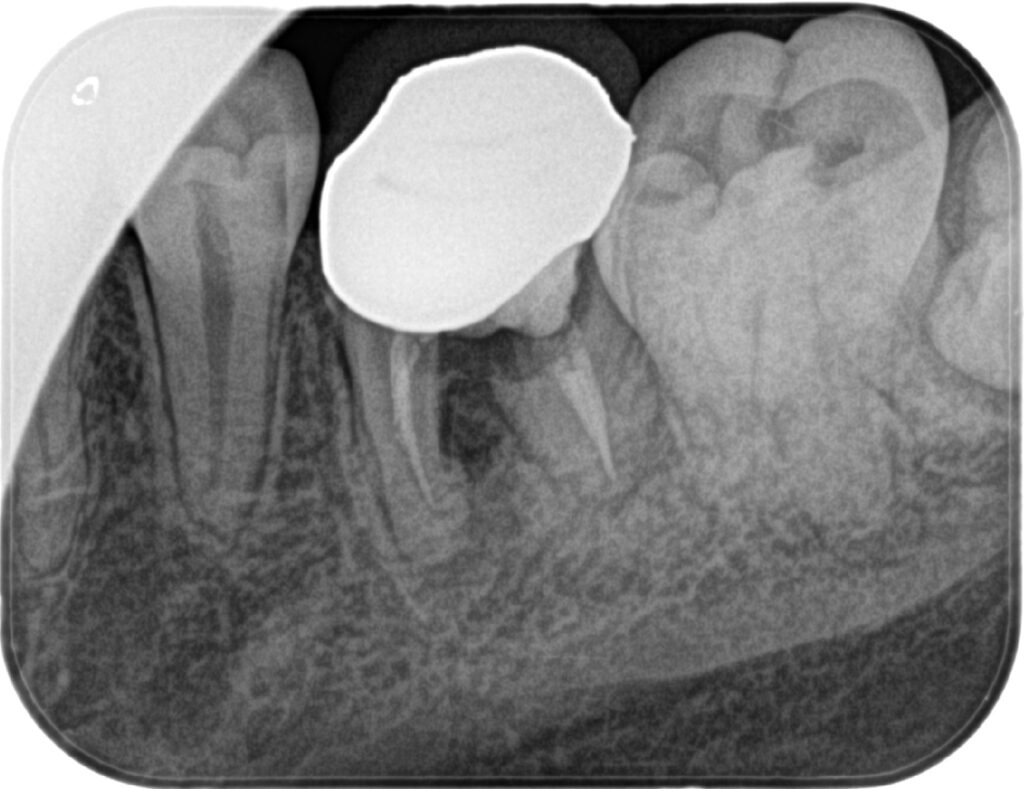

| 主訴 | 左下の被せ物のところの匂いが消えない。違和感があるので見てほしい |

| 年齢 | 20代男性 |

| 治療内容 | 歯質と補綴物の不適合あり。CT撮影を行って確認したが残すことが難しい為インプラント治療へ。 最終的なかぶせものはご自身の歯と変わらないような仕上がりとなっています。 |

| 抜歯部位 | 左下6 |